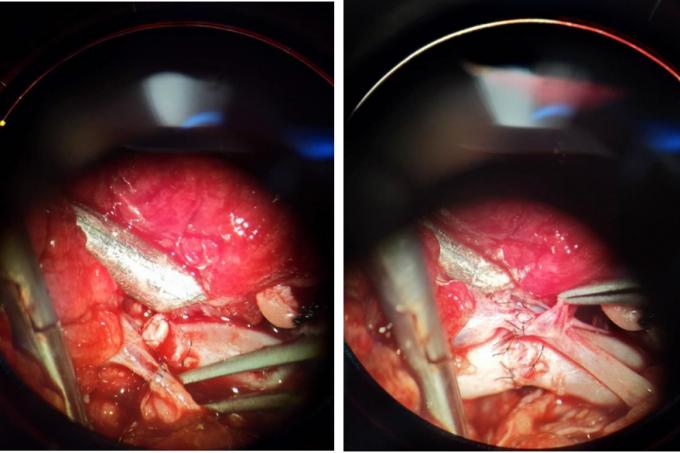

伤情复杂,刻不容缓!“在纠正生命体征的同时,进行保肢。同时,保肢手术难度在于血管的吻合、骨、神经肌腱的修复,需要高超的显微外科技术才能完成修复工作。”危急时刻,创伤外科一病区科室团队最终决定:快速输血、输液,纠正失血性休克,在生命各项体征基本稳定前提下,为患者进行保肢手术,以尽最大可能保住肢体。张亮主任一边安排患者进行必要的术前检查,紧急与麻醉科联系,立即展开手术。术中,行彻底清创、骨折复位外架固定,血管、神经、肌肉探查修复,经9小时紧急抢救,手术顺利完成。

主任介绍说,断肢再植手术的难度在于:一是要重建血供,将静脉、动脉等血管重新精细地缝合,血管吻合后,需要血液能够通过,才能恢复血供,断肢得以存活;二是,下肢是活动的,有屈伸功能,除骨头外,还有多根肌腱、神经均需要一对一地修复重建,才能最大程度保证再植肢体术后功能的恢复。这些精细化的修复,都需要在显微镜下完成,时间长,耗费体力大。”

“肢体保住了,这只是个良好的开始。对这种难愈性创面的治疗更是关键。”在一期手术后,患者整体血运良好,但局部部分皮肤软组织坏死,伤口没有完全愈合,因此需要进行扩创修复创面。最终经局部皮瓣转移、植皮,伤口得到全面愈合,为后期再植肢体功能恢复打下了良好地基础。